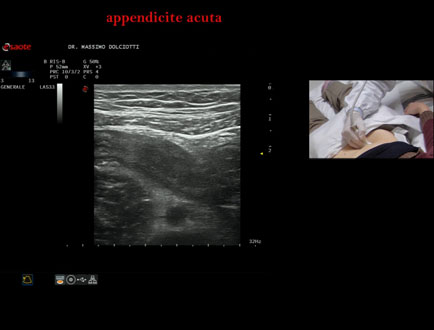

Data inserimento: 15/01/2026

Ecografia del: 07/01/2025

Strumento: Esaote MyLab Eight

Sonda: Lineare Multifrequenza 3-13 MHz

Età Paziente: F 39 anni

Motivazione dell'esame: dolori addominali epiastrici da 2 gg, anche notturni, non nausea, non vomito, non diarrea, non febbre, diuresi normale, nicturia saltuariamente.

Commento all'esame: le immagini ed il video documentano, in sede ileo-cecale, appendice di spessore aumentato (11 mm - V.N. inferiore a 6 mm). Gli elementi ecografici segnalati orientano per appendicite acuta.

Conclusioni: appendicite acuta (acute appendicitis).

In collaborazione: Dr.ssa Marica Manfredi - Ancona, Dr. Ilir Qose - Ancona

Presentazione: Dr. Massimo Dolciotti - Ancona

Elaborazione digitale: Andrea Dini - Ancona